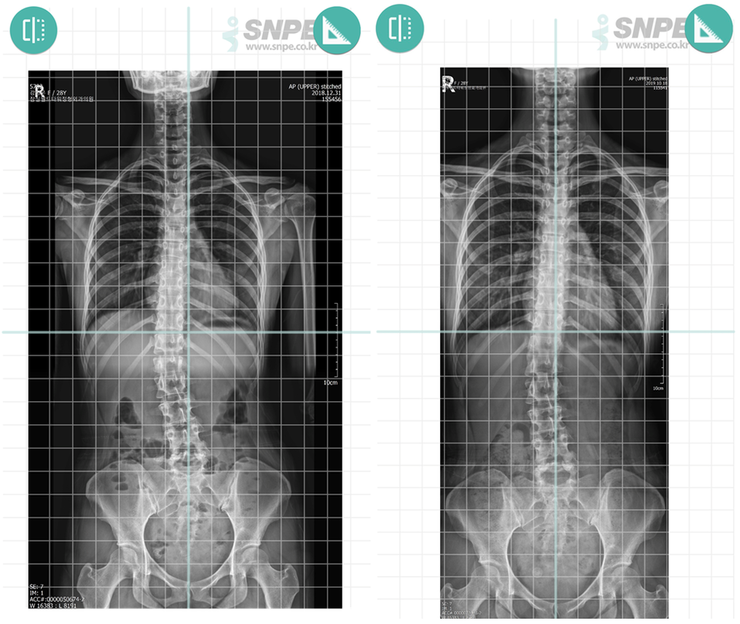

[     X-ray 사진 -척추측만증 개선    ]

왼쪽 2018년 12월 31일 / 오른쪽 2019년 10월 18일

X-ray 사진을 보니 척추측만증이 개선된 것이 눈에 확 띕니다.

왼쪽 사진을 보면 치골결합을 중심으로 수직선을 그어봤을 때에 경추가 선을 벗어나 있었는데요!

SNPE 운동 후에는  경추가 중심선 안에 들어왔습니다. 하부흉추과 요추를 조금 더 바로 세워야 하겠지요.